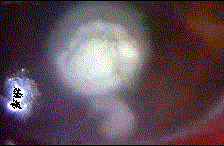

问题 患者,男性农民,右眼被谷物弹伤,视物模糊1个月就诊。检查:右眼视力0.5,结膜充血,角膜有黄白色病灶,污秽,伴前房积脓。 最可能的诊断是 (如图) ( )

选项 A、病毒性角膜溃疡 B、淋菌性角膜溃疡 C、真菌性角膜溃疡 D、蚕食性角膜溃疡 E、铜绿假单胞菌(绿脓杆菌)性角膜溃疡

答案 C